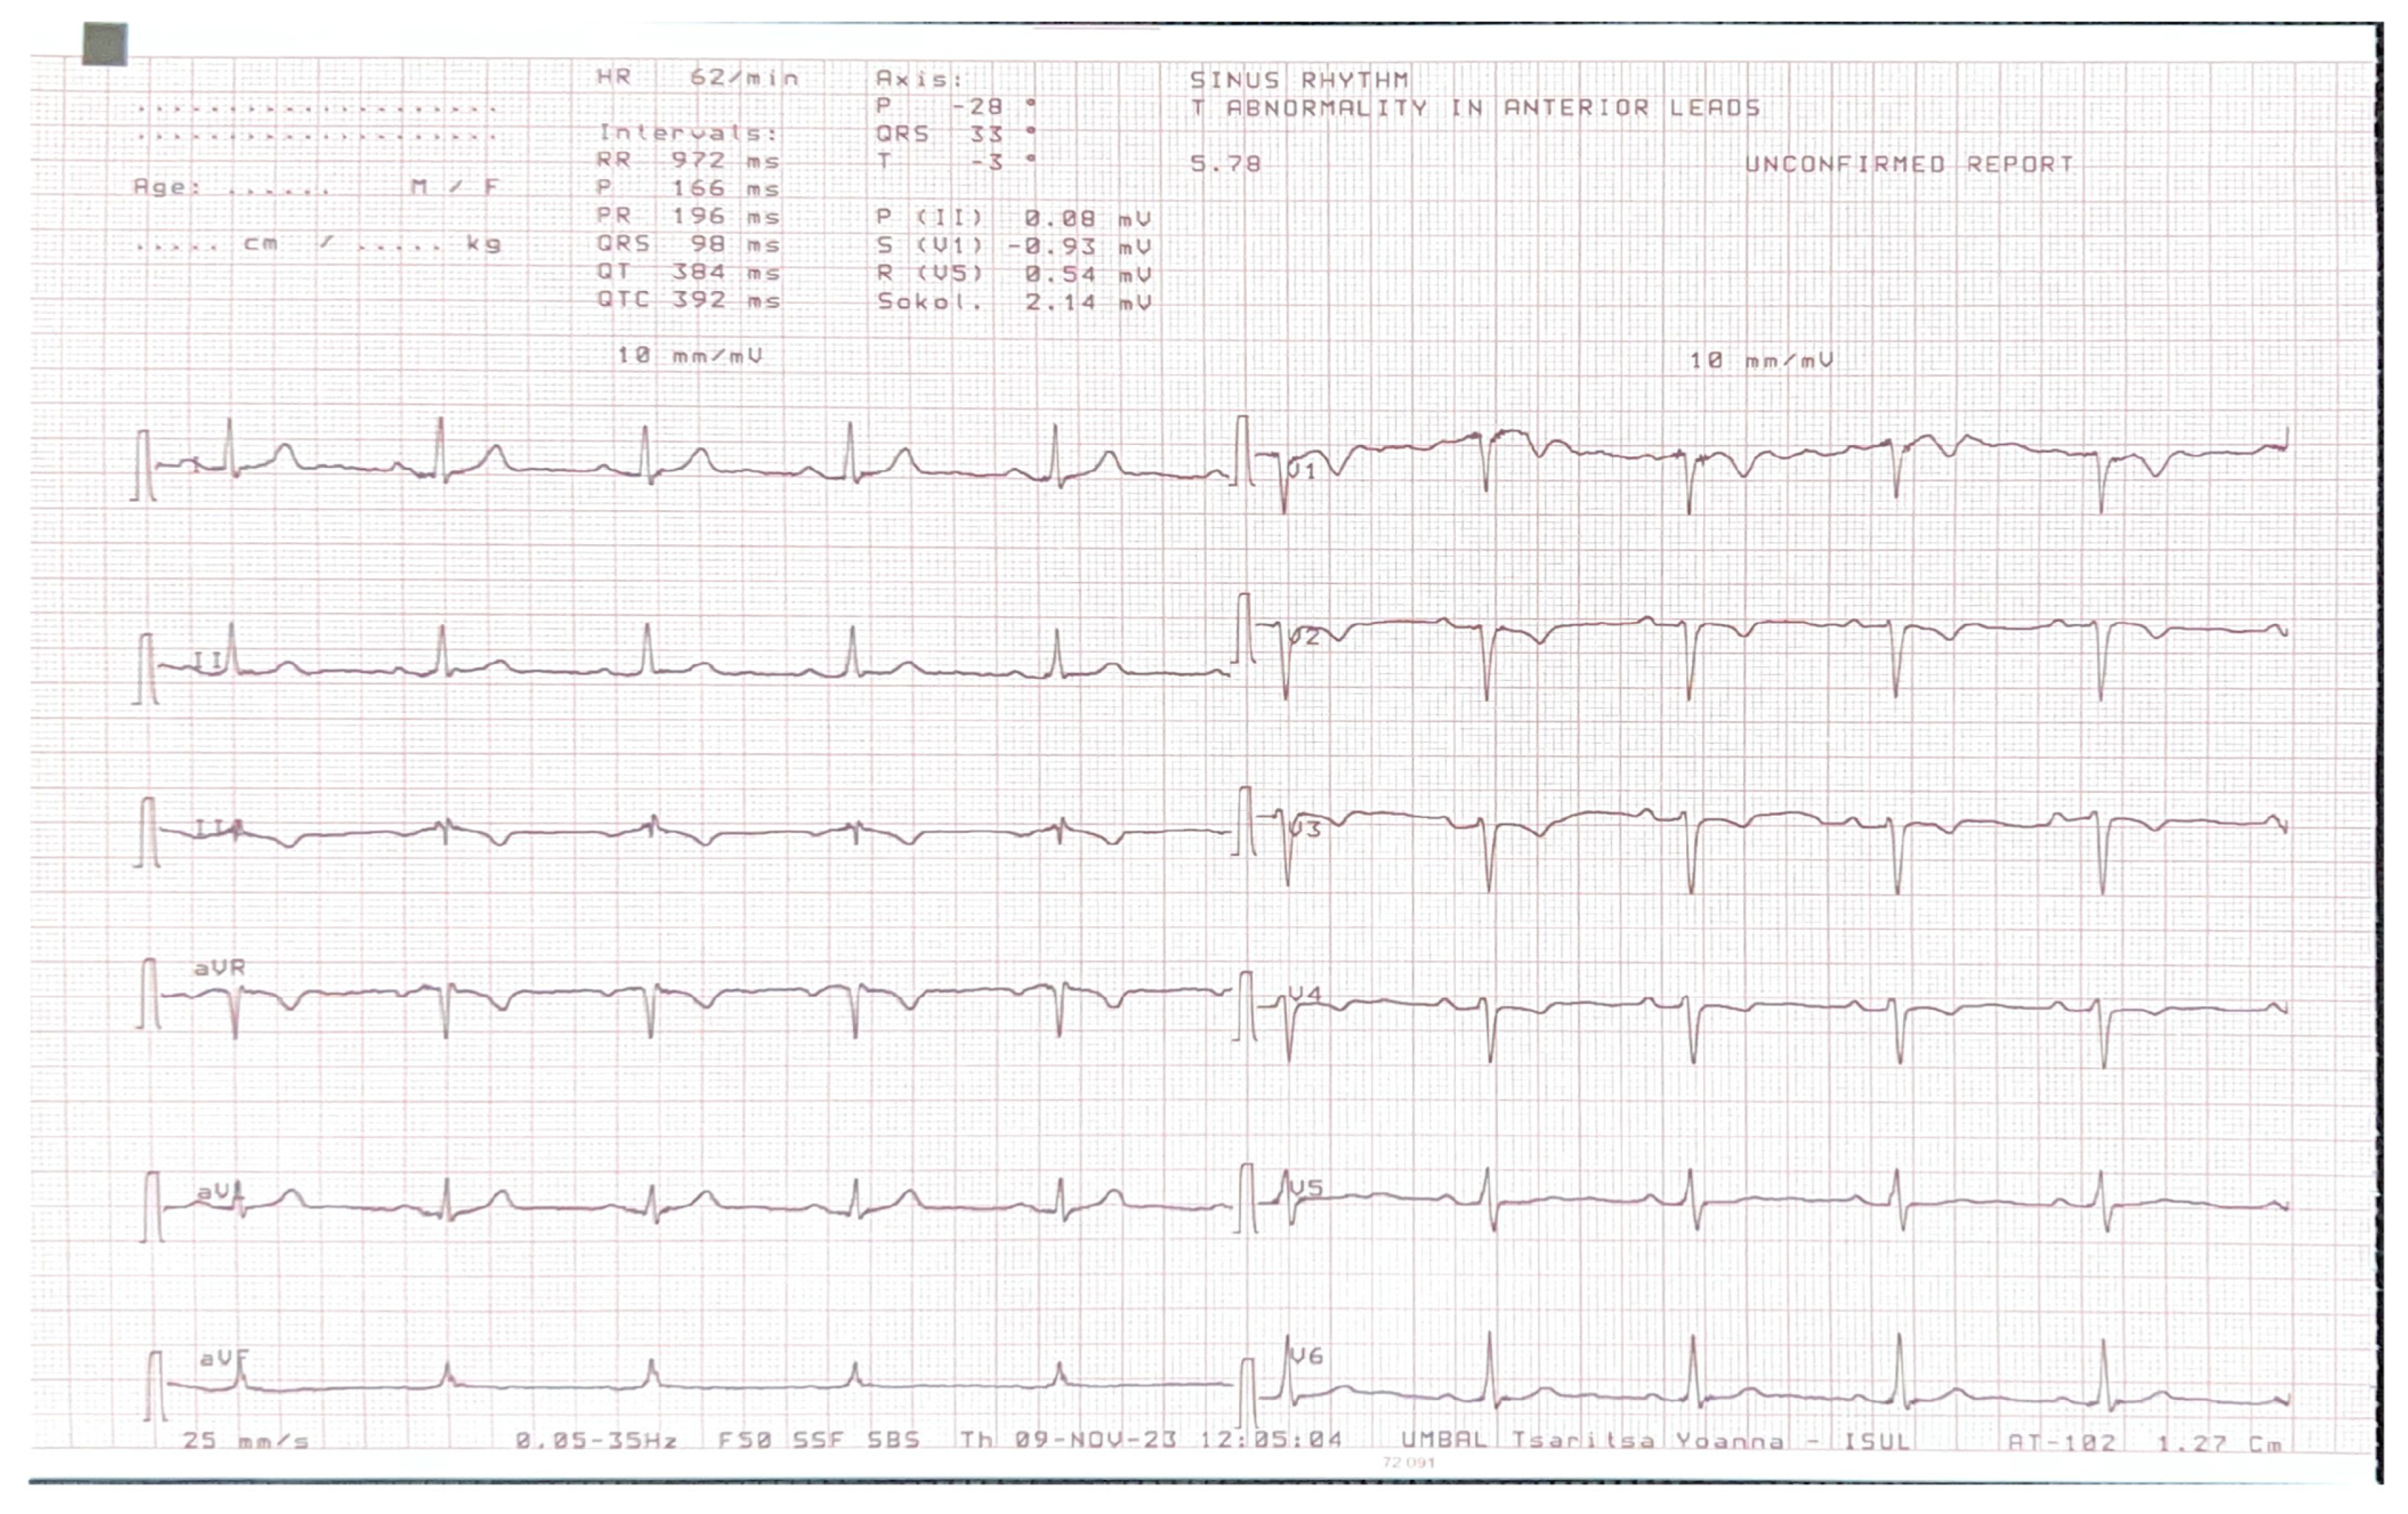

A 36-year-old male with first grade essential arterial hypertension with good medical control was referred for routine cardiovascular exam. He had a medical history of heart murmur since childhood and has been told to have interventricular communication. No prior medical records were submitted. Physical examination did not demonstrate any cardio-pulmonary abnormalities. An electrocardiogram (ECG) revealed sinus rhythm at 62 bpm, normal axis, poor R-wave progression in the precordial leads and repolarization abnormalities and negative T waves in V1–V4 (Figure 1).

Figure 1.

ECG of the patient.